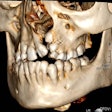

Planmeca integrates software with intraoral scanners